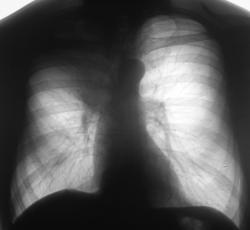

Иллюстрация 3. Поднят «архив». Цифровая флюорограмма за 2007 год.